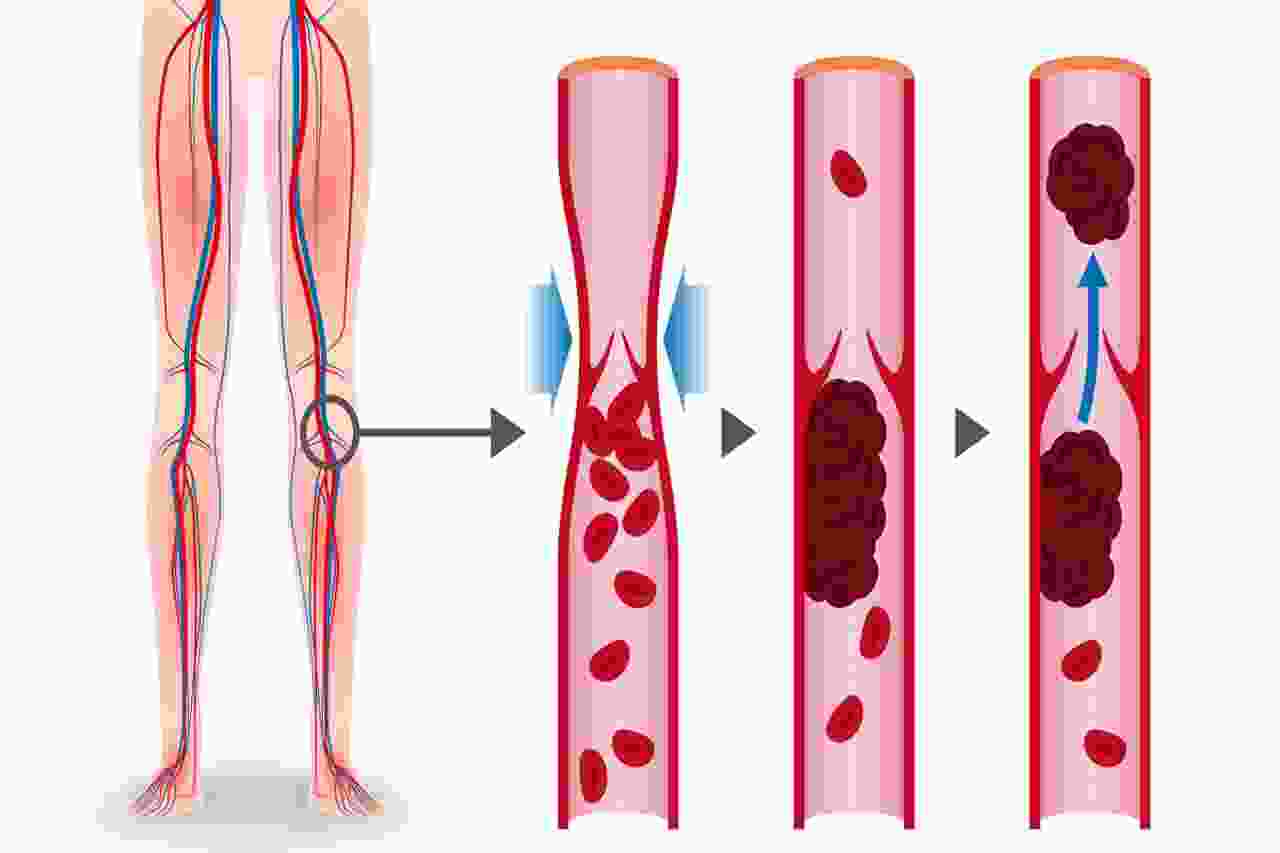

الجلطات الوريدية

الجلطات الوريدية هي خثرة دموية داخل الأوردة، غالبًا في الساقين